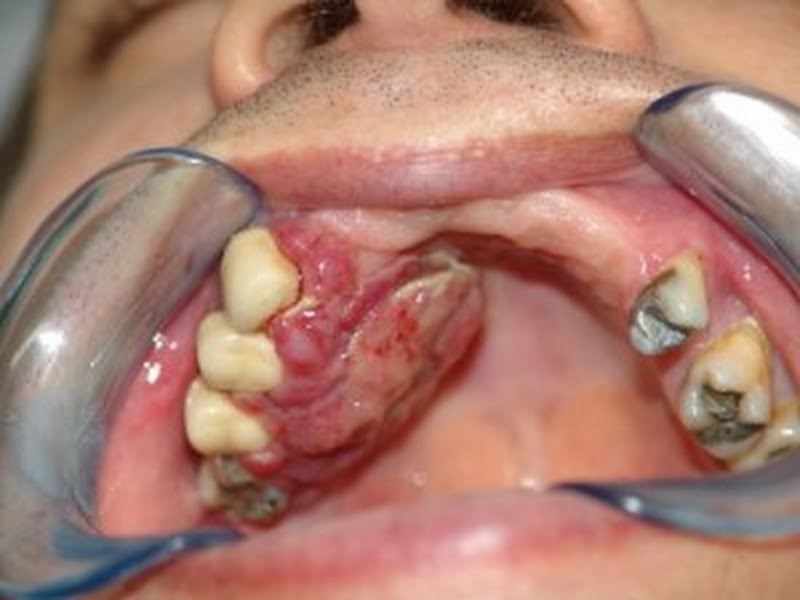

De acordo com a Divisão Municipal de Odontologia, todos os postos que possuem atendimento odontológico estão aptos a fazer o exame. O cirurgião-dentista fará um exame superficial à procura de possíveis lesões e de agentes causadores do câncer bucal.

Caso o cirurgião-dentista detecte alguma lesão o paciente será encaminhado para exames mais detalhados, incluindo até se necessário o tratamento. Na oportunidade, os profissionais também estarão orientando os pacientes sobre como se prevenir contra o câncer bucal e quais os agentes causadores.